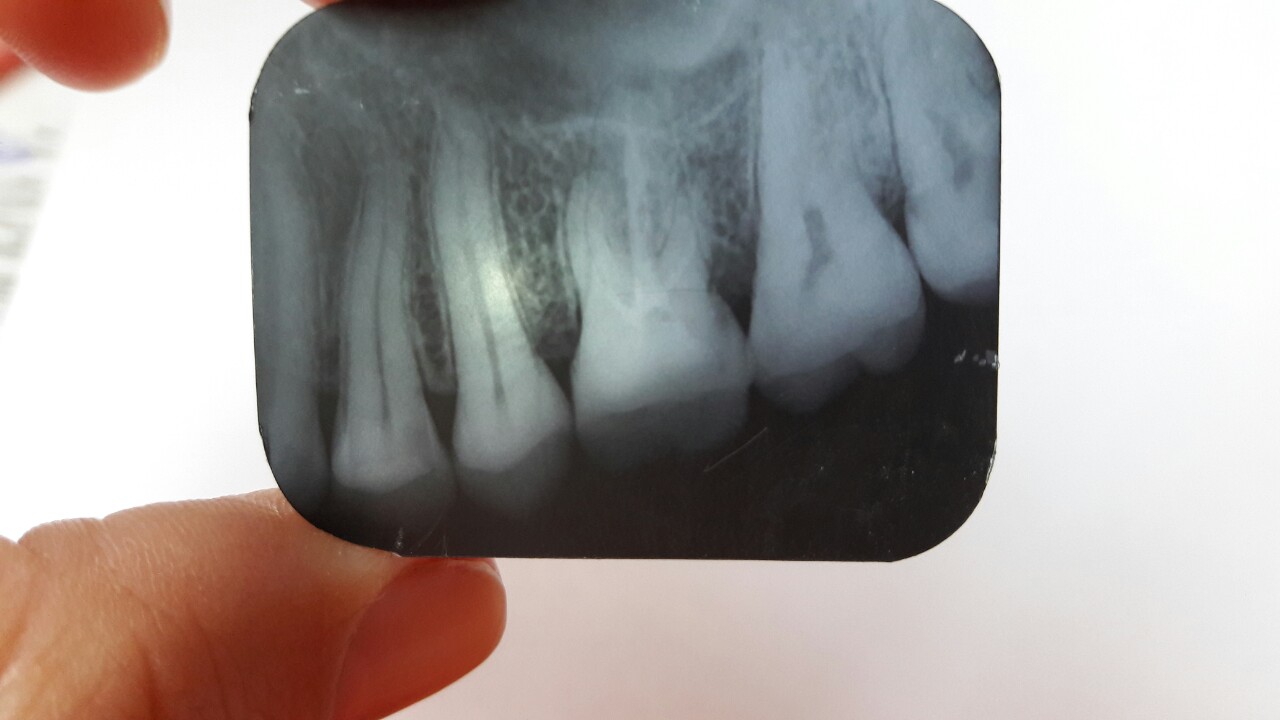

Добрый день, делала зуб, шестерку, начал болеть через 2 недели. Боль была очень сильная, у моего доктора смена закончилась, пошла к другому. После осмотра выяснилось, что воспалилась восьмерка, это она давала боль, отправили на удаление, но перед этим на рентген и восьмерки и на всякий случай и шестерки. И тут выяснилось что шестерку нужно переделывать, сказали идти к доктору, который делал . Я попыталась сфоткать рентген, подскажите пожалуйста, что не так и стоит ли идти переделывать к этому врачу, может опять что-то не так сделает, боюсь чтобы зуб не развалился от такого лечения. Тем более за кариозную восьмерку он промолчал. Не знаю что делатьНажмите на изображение для увеличения

...некачественная пломбировка каналов...на медиально-щечном корне - гранулема, поэтому шестой зуб вполне мог болеть из-за обострения хронического воспаления на корне... К слову, в этом зубе в 95% четыре канала, и четвертый канал, как раз в указанном корне...